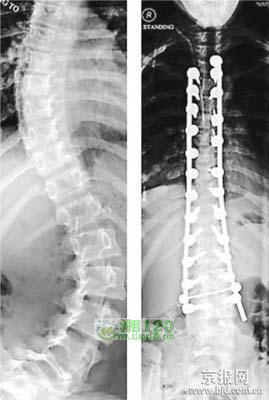

据英国媒体报道,英国多塞特郡浦尔市16岁少女乔丝·查普曼两年前患上了一种罕见的脊柱侧凸症,导致她的脊椎变成了扭曲的S形,胸腔甚至能触碰到骨盆。不过,英国南安普敦综合医院的专家通过10小时的先锋性手术,却奇迹般地拉直了乔丝的弯脊梁,使她一下子长高了13厘米,在一夜之间变成了一个身材高挑的美少女。

几个月前,英国南安普敦综合医院的专家决定对乔丝实施先锋性的拉直脊梁手术。专家通过10小时的手术,将两根钛棒用铆钉固定到了乔丝的扭曲脊椎上,几乎就拉直了乔丝的弯脊梁。当医生得知乔丝拥有当模特的梦想后,他们又敲断了乔丝的4根肋骨,从而使她凸起的后背重新变平,专家还在乔丝的断骨间插入了一些小弹簧。